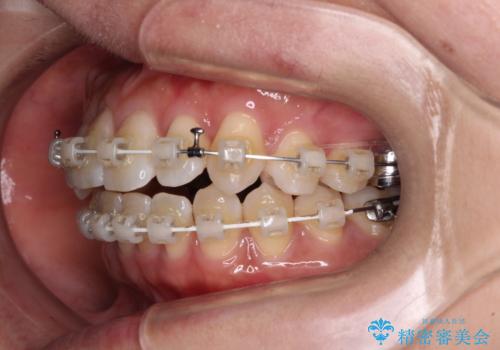

- 審美装置

口元の突出感はなかったため非抜歯矯正での対応となりますが、八重歯を改善する際に上顎前歯が前突する可能性があったため、上顎臼歯部にアンカースクリューを使用して、歯列が前方に転位しないようにすることとしました。

ワイヤー矯正でもインビザラインでも対応可能でしたが、上顎歯列が前方位であるときには、ワイヤー矯正の方がより良い仕上がりとなる可能性が高いため、ワイヤー矯正をおすすめいたしました。